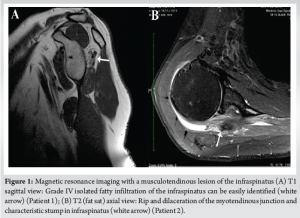

The first patient (Patient 1), a 57-year-old athletic female, experienced the onset of subacromial impingement in her non-dominant shoulder 10 years before presentation, accompanied by posterior calcific tendinopathy. Initial treatment involved barbotage and several subacromial injections, which provided temporary relief for a few months. However, the patient continued to have trouble performing daily activities, with a preoperative visual analog scale (VAS) score of 8. Preoperative active forward elevation (FE) was 60°, with 0° of active external rotation with the elbow at the side (ER1). She exhibited a positive external rotation lag sign exceeding 40°, as well as positive drop sign, with strength in ER1 measured at 0/5. Magnetic resonance imaging (MRI) revealed an isolated musculotendinous lesion in the infraspinatus, associated with calcific tendinopathy and grade IV fatty infiltration (Fig. 1a). The remaining rotator cuff tendons were intact.

The second patient (Patient 2), a 66-year-old male, experienced pain in his right dominant shoulder several years before presentation. Despite conservative treatment, the patient continued to complain of extreme shoulder pain, with the preoperative VAS score at 9. Regarding preoperative range of motion (ROM), active FE was limited to 40°, and active ER1 was at −15°. A significant external rotation lag sign was observed, the drop sign was positive, and the patient exhibited poor strength in ER1 (1/5) (Fig. 2a and b). MRI results indicated isolated grade IV fatty infiltration of the infraspinatus, ripping (dilaceration) of the musculotendinous junction, and the characteristic stump (Fig. 1b). There were no signs of tear in the remaining rotator cuff.